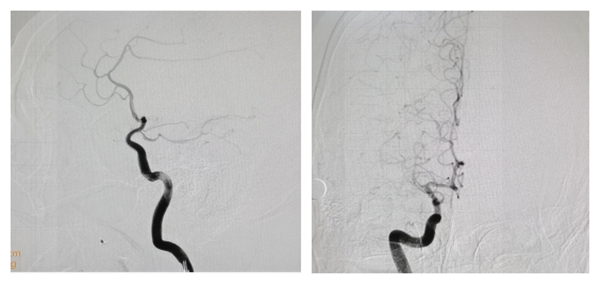

术前造影显示右侧大脑中动脉M1段闭塞

术后右侧大脑中动脉开通,远端血供恢复